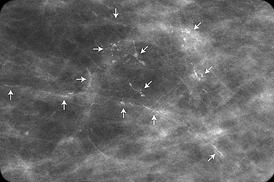

What they saw on my scans was a splattering of salt-grain-sized microcalcifications on my left breast. In such cases, they need to take a closer look to make sure there aren’t any red-flag patterns, like tight clusters or irregular shapes.

This isn’t my scan, but it’s an example of the early “lining up” pattern they don’t want to see.